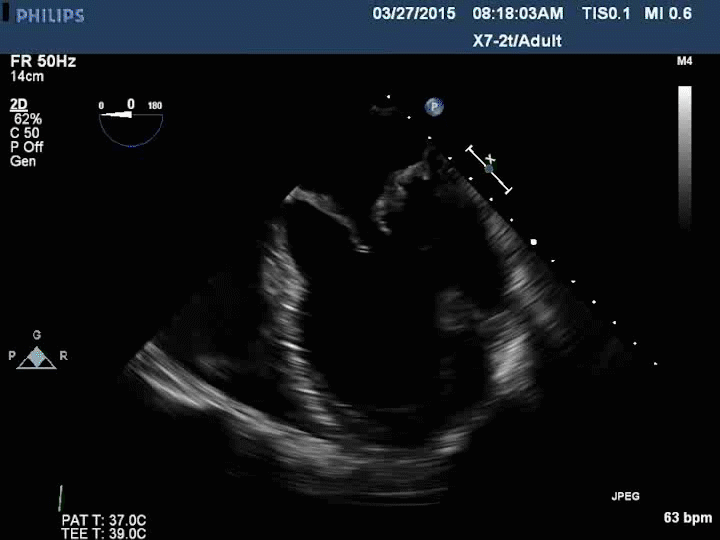

Fig 1: Echocardiography with doppler

Two-dimensional and Doppler echocardiography is essential to determine the mechanism (dysfunction) and severity of mitral regurgitation. Assessment of the mitral valve hemodynamics using the ratio of jet to left atrial area 1, the regurgitant volume (Rvol: the difference between the mitral and aortic stroke volumes) and effective regurgitant orifice (ERO: ratio of regurgitant volume to regurgitant time velocity integral) are useful tools in grading the severity of MR (Table 12), when integrated with clinical findings. Recent guidelines published by the AHA/ACC joint committee propose a more integrative MR severity grading system ranging from grade A (least severe) to grade C, which defines MR as at risk, progressive, asymptomatic severe and symptomatic severe (Table 2)3

Transesophageal echocardiography (TEE) is a useful adjunct to confirm the diagnosis and understand the mechanism of degenerative valve disease in the case of a non-diagnostic transthoracic examination. Experience is also gaining with 3-dimensional echocardiography in the assessment of annular geometry and leaflet dysfunction in the setting of mitral regurgitation, and can be predicted to have a more significant role in planning reparative procedures in the future.